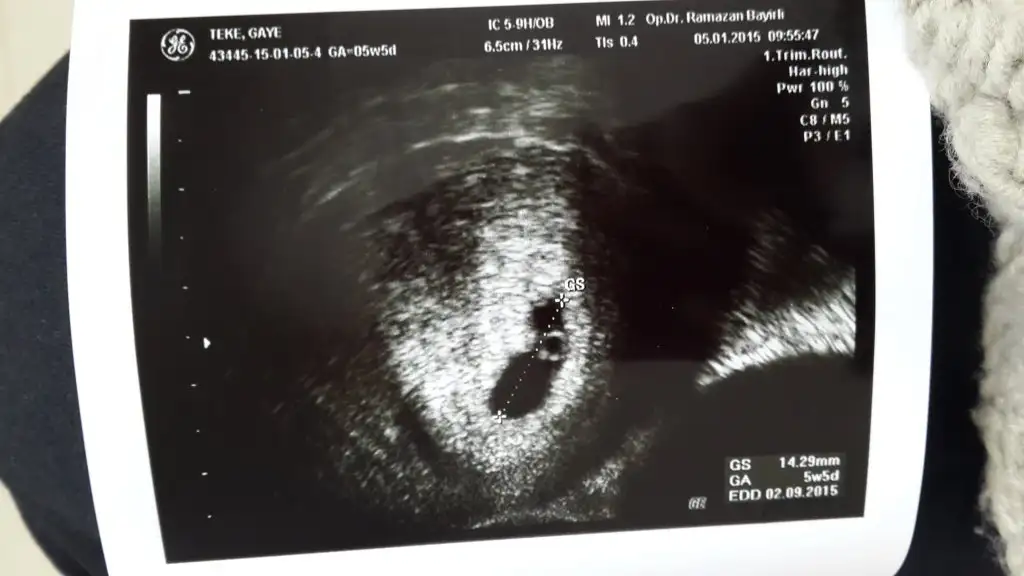

Az önce geldim doktordan vajinal ultrason ile 1.5 cm lik kesemizi ve yolk saçı gördük çok şükür.. 5+5 günlük ve % 90 sagliklı bir gebelik dedi doktorum. Ultrason görüntüsunu de ekliyorum aşağıya :) Daha önceden düşugum olduğu için progestan jel kullanıyorum.. haftaya kalp atışı için gidicem tekrar.. umarım sağlıkla kavuşuruz meleklerimize hepimiz

Çok teşekkürler ben de ilkinde kalp atışı duyamamistim ama onun öncesinde yolk saç 5.5 mm çıkmıştı ozaman doktor yolk sac cok buyuk sağlıksız gibi duruyor demişti zaten sonra da kalp atışı oluşmadı.. Bu kez doktora hemen yolk saçın buyuklugünü sordum allahtan 3.3 mm dedi ilk aşamayı geçirdiğim için iiçim rahatladi.. şimdi sıra kalp atisinda inşallah hayirlisiyla hepimiz duyarız bebislerimizin kalp atislarini